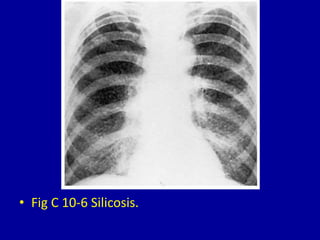

The document describes and shows images of 11 different conditions that present with miliary nodules on clinical imaging of the lungs. These conditions include tuberculosis, coccidioidomycosis, histoplasmosis, metastatic thyroid carcinoma, alveolar cell carcinoma, silicosis, coal-workers' pneumoconiosis, chickenpox pneumonia, pulmonary hemosiderosis, schistosomiasis, and listeriosis. For each condition, the document shows one or more chest x-ray images demonstrating the miliary nodule pattern involved in the lungs.